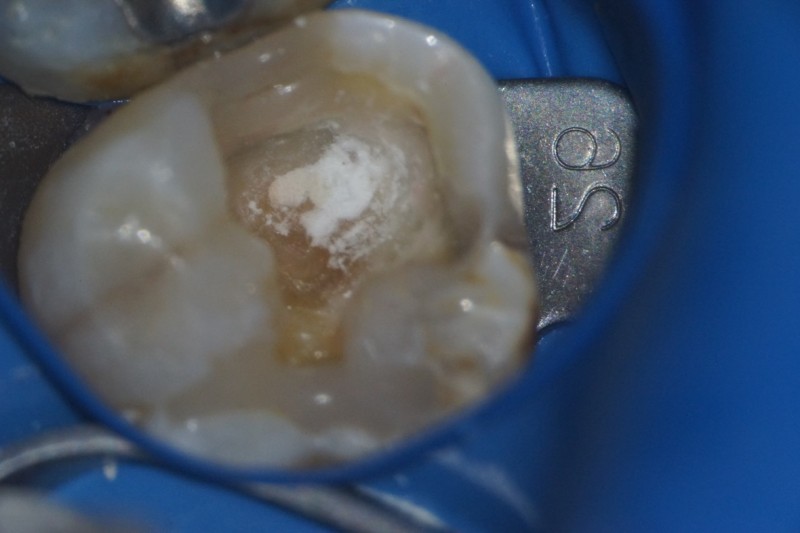

こちらの患者さん、半年前に詰め物が外れたまま放置されてましたが、徐々に痛くなってきたので来院されました。詰め物が外れた時点で、かなり深い虫歯になっていたことが予想されます。

レントゲンの、赤丸のところが虫歯になっています。神経に届きそうなほど深いです。

虫歯菌に感染しているところを染めてみると、真っ赤になります。

赤い部分を取り除く前に、唾液の侵入を防ぐために壁を作ります。

そのあと、虫歯を取り除いていくと、神経が露出しました。出血しているので、神経はまだ生きています。

神経が露出したところに、MTAという神経を保護できるセメントをつめて様子を見ます。